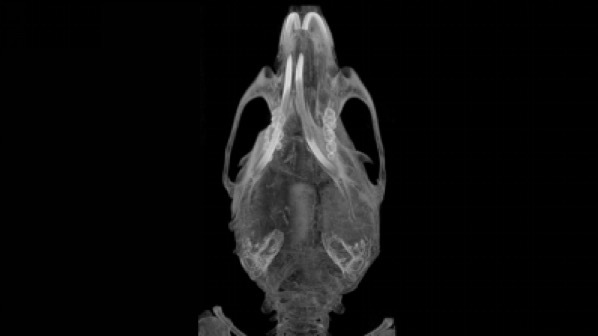

近日,中大五院广东省生物医学影像重点实验室通过对非转基因小鼠尾静脉注射18F标记的FDG,利用小动物PET/CT,获得了小鼠高清全身18F-FDG PET动态扫描图像与数据。这意味着,小动物PET/CT将为临床疗效评价和肿瘤监测,提供了有效观察方法。

中大五院广东省生物医学影像重点实验室金红军研究员介绍,对小鼠尾静脉注射18F标记的FDG后,通过特定的生物技术分析平台,可进行动态数据采集和重建,观察到第1秒到1小时后18F-FDG的小鼠体内的分布变化。分析上述动态数据可获得18F-FDG进入小鼠体内以后在各组织器官的分布和代谢情况,得到小鼠组织器官对该药物代谢的时间活度曲线。